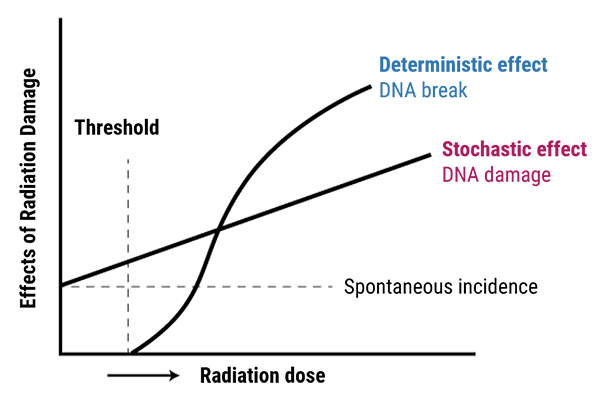

As we mentioned earlier, ionizing radiation damages DNA and has harmful effects on human tissues. These effects can be classified into stochastic and non stochastic effects.

Stochastic effects occur in a linear manner; this risk of injury increases as the dose increases, and the effects are cumulative. They occur by chance with a probability proportional to the dose, and a severity independent of the dose. The most significant risk is cancer.

Non stochastic effects are the same as deterministic effects. They are those for which incidence and severity depends on dose. In fact, after a certain threshold has been met, non stochastic effects occur.

This threshold is the limit at which the organ will be damaged with a polynomial function response.

Exposure to very high levels of radiation, such as being close to an atomic blast, can cause acute health effects such as skin burns and acute radiation syndrome (“radiation sickness”). It can also result in long-term health effects such as cancer and cardiovascular disease, if the radiation is in a moderate levels (100-1000 mSv). And finally no symptoms and no detectable risk of cancer are seen if the radiation is in tolerable level (0.1-20 mSv).